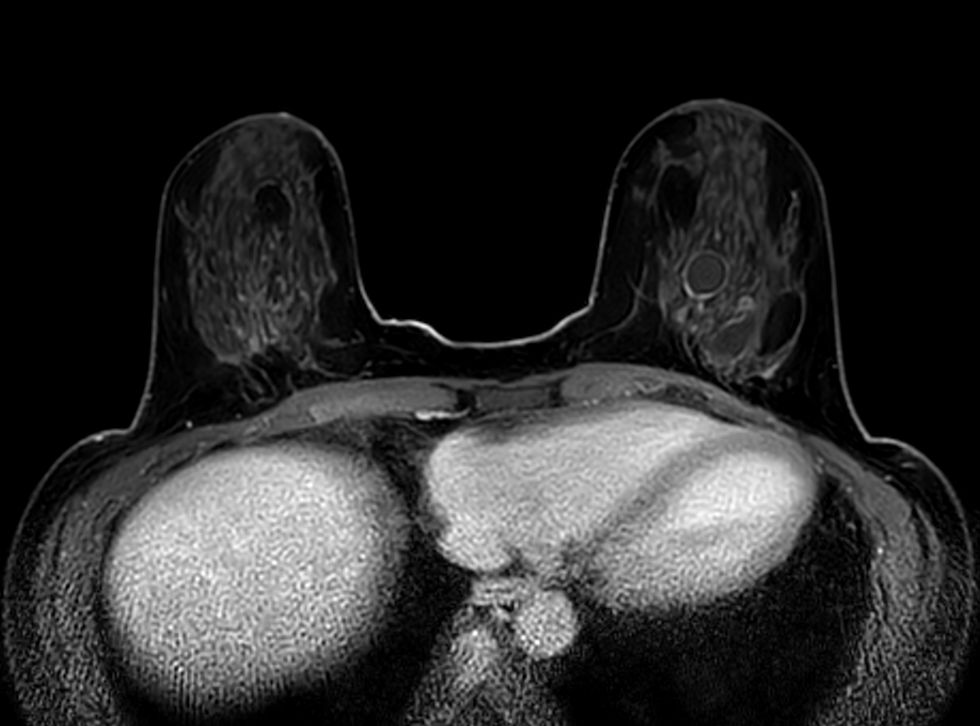

Axial 3D VANE XD

3D VANE XD (coronal reformat)

3D VANE XD (sagital reformat)

3D Breast imaging lets you acquire high resolution data in multiple directions, including oblique, in one scan helping you enhance your confidence when diagnosing lesions. 4D FreeBreathing provides dynamic information with a high temporal resolution, allowing contrast-enhanced MRI breast studies.